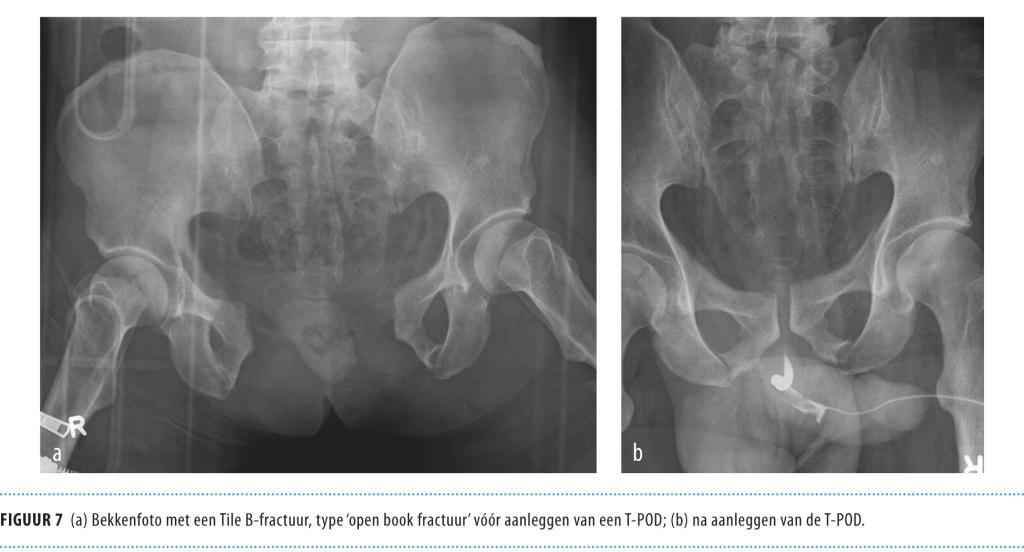

Op de thoraxfoto constateerden wij een pneumothorax rechts, waarvoor we een thoraxdrain inbrachten. Er waren geen aanwijzingen voor een hematothorax. Echografie van de buik gaf geen aanwijzingen voor vrij vocht. Op de bekkenfoto zagen wij een volledig instabiele bekkenfractuur (type ‘openbook’) met een acetabulumfractuur rechts. We legden direct een T-POD aan en startten met transfusie van 4 eenheden packed cells. De bloeddruk steeg hierop naar 100/60 mmHg met een polsfrequentie van 100/min.

Afhankelijk van de hemodynamische situatie zijn verschillende behandelingsopties mogelijk. Verkleining van het bekkenvolume kan zowel non-invasief: door een sluitlaken aan te leggen (figuur 7), als invasief: door gebruik te maken van een externe fixateur (C-clamp). In het geval dat hiermee de bloeding niet onder controle gebracht kan worden, is bij een ernstige hypovolemische shock (persisterende hypotensie 5

Figuur 7

• ‘Open book’-fractuur: bekkenfractuur met doorgescheurde symfyse. Het bekken kan als het ware als een boek opengeklapt worden.